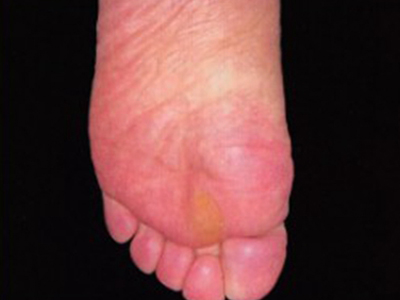

胼胝俗称老茧,是由于长期受压和摩擦部位发生硬而平滑的角质增生性皮肤病,好发于掌跖受压迫和摩擦处。一般不影响健康和劳动,反而可起到一定的保护作用,可有压痛及碰撞痛。

胼胝表现为黄色或蜡黄色增厚的角质性斑块,偏平或稍隆起,中央较厚边缘薄,质地坚实,边界不清,表面光滑且皮纹清晰。局部汗液分泌减少,感觉迟钝,多无自觉症状,严重者可疼痛。

胼胝多为患处长期受压、摩擦所致,常发于足跖,尤其是骨骼突出部位。本病与患者的身体素质、足畸形或职业有关。